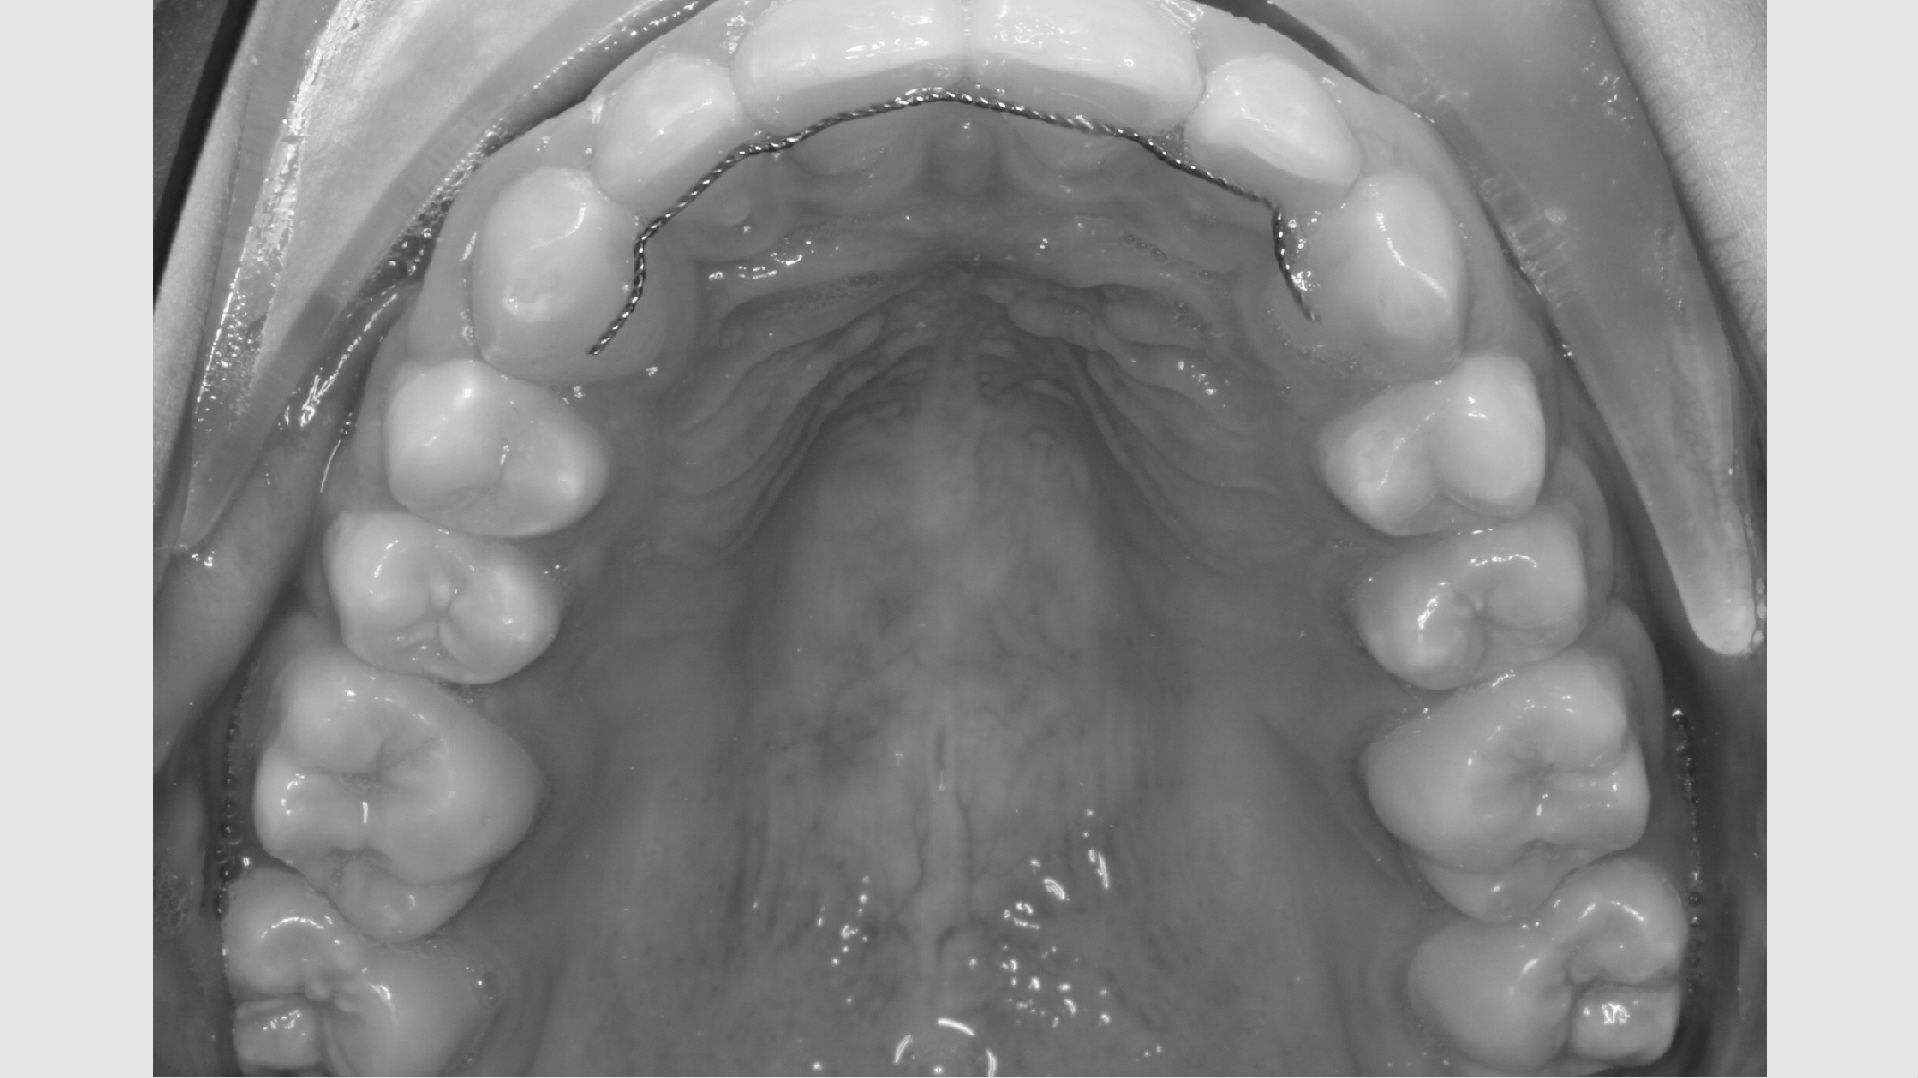

Første gang dit barn besøger Tandreguleringsklinikken, bliver der lavet studiemateriale.

Studiemateriale, består af modeller, fotos og røntgenbilleder af tænder og ansigt. Der bliver også udleveret et helbredsskema, som skal udfyldes på stedet. Det er vigtigt at vide, om jeres barn er sundt og raskt, eller om der er særlige hensyn, vi skal tage - eksempelvis til medicin med videre.

Der bliver taget billeder "udenpå og indeni" samt røntgenbilleder.

Dit barn skal selv holde sine læber til side med en læbeholder, mens tænderne bliver fotograferet. Billederne har følgende formål: